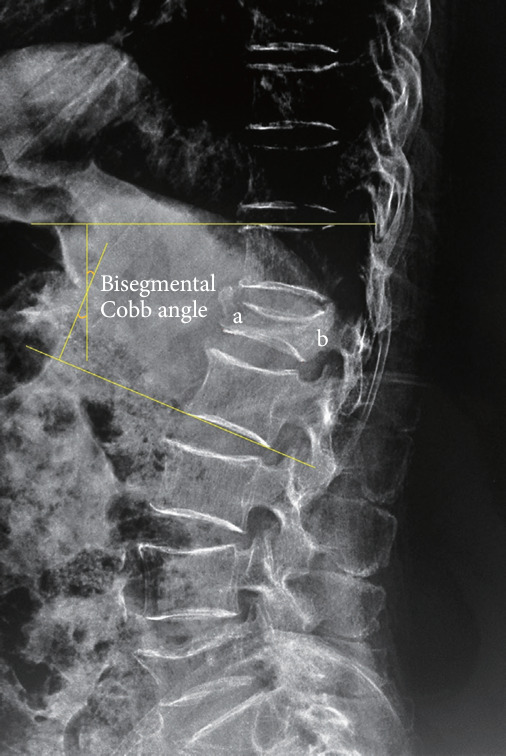

Methods: From May 2017 to May 2021, 77 patients with single-level unstable KD were included in the PPP group, and 42 patients received the PVP-bone cement bridging screw system were included in the screw group. The changes in the vertebral body index (VBI), bisegmental Cobb angle, visual analogue scale (VAS) and Oswestry Disability Index (ODI) and the cement loosening rate and displacement rate at different follow-up time points were used to evaluate the clinical efficacy.

Results: There was no significant difference in VBI or bisegmental Cobb angle between the 2 groups (p > 0.05) before operation, immediately after operation and at 6-month followup, while at 1-year and 2-year postoperative evaluations, the screw group had higher VBI and bisegmental Cobb angle than the PPP group (p < 0.05). Before operation, immediately after operation, at 6-month and 1-year follow-up, there was no significant difference in VAS or ODI score between the 2 groups (p > 0.05), while at 2-year follow-up, the screw group still had higher VAS and ODI scores than the PPP group (p < 0.05). No bone cement displacement occurred in both groups, but the rate of bone cement loosening was 14.29% in group PPP, and 0 in screw group (p < 0.05).